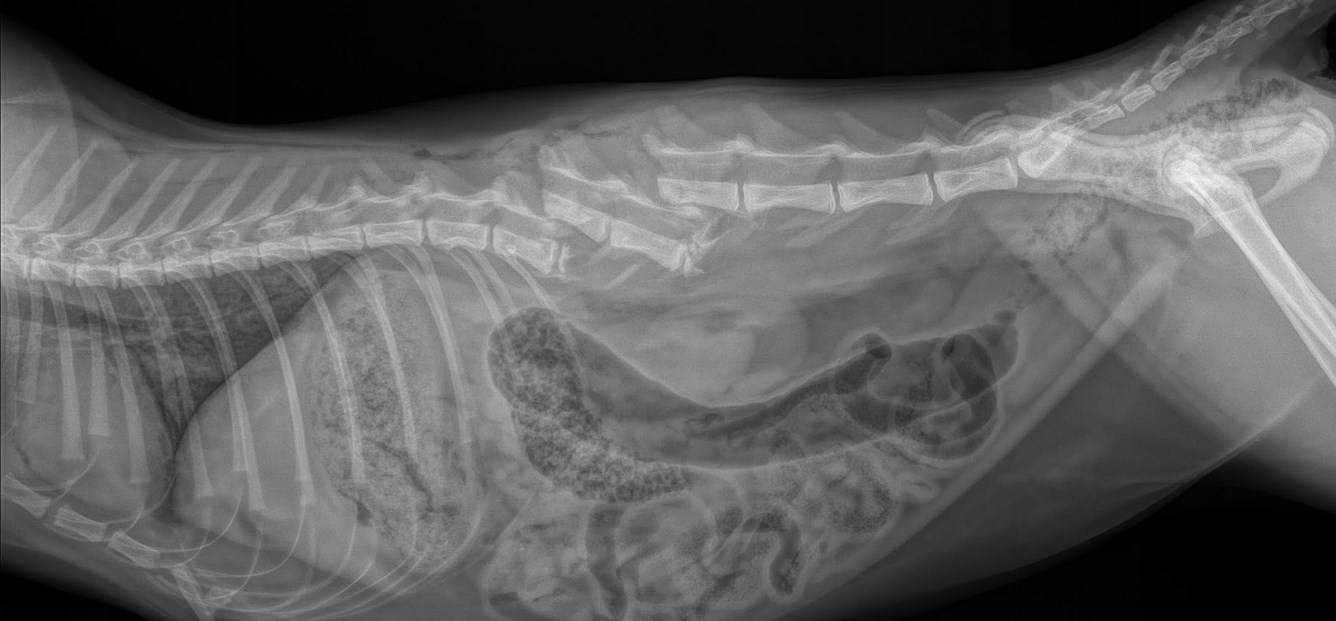

Эктопия мочеточников – разновидность тяжелого врожденного заболевания, которое не щадит ни взрослых собак, ни щенков. Характерные признаки могут отмечаться уже в щенячьем возрасте по симптоматике, определить которые может квалифицированный специалист. Зачастую после урографии требуется хирургическое вмешательство и послеоперационная терапия до полного выздоровления

Эктопия

Эктопия – это врожденное заболевание, которое и служит причиной учащенного мочеиспускания. Диагностируется на основании результатов сданных анализов. В большинстве случаев заболевание диагностируется у собак женского пола. Порой для лечения недуга необходимо хирургическое вмешательство, в некоторых случаях используют урографию.